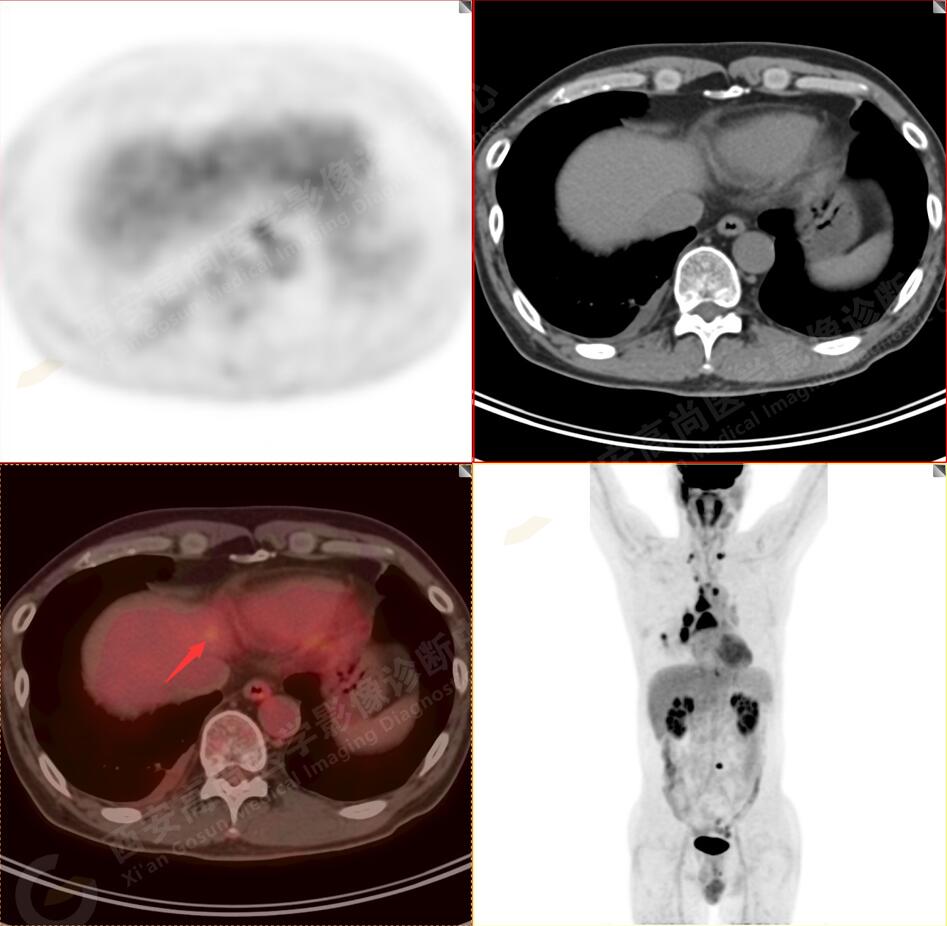

2.以下為全身多發(fā)轉(zhuǎn)移灶

2.雙肺多發(fā)高密度小結(jié)節(jié)灶(最大徑約0.7cm),部分較大結(jié)節(jié)呈FDG代謝略增高,均考慮為轉(zhuǎn)移性病變。

4.右后胸膜輕度增厚,形成多個(gè)條狀軟組織病變,呈FDG代謝輕度異常增高,考慮為轉(zhuǎn)移性病變;右側(cè)胸腔微量積液。